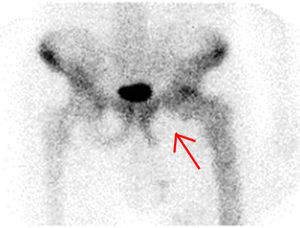

Presentamos el caso de un paciente varón de 82 años diagnosticado 10 años antes de enfermedad de Paget ósea con afectación poliostótica. Como otros antecedentes de interés presentaba fibrilación auricular e insuficiencia cardiaca crónica. Acudió a la unidad y consulta de atención inmediata (UCAI) por astenia, anorexia y edemas en las extremidades inferiores de 15 días de evolución. En la anamnesis por aparatos refería dolor en la región isquiopubiana izquierda desde hacía 6 meses, que había ido en aumento y que aparecía tanto en reposo como con el ejercicio. Se decidió ingreso en planta de hospitalización para tratamiento de la insuficiencia cardiaca y estudio del origen del dolor. En la exploración física presentaba palidez de piel y mucosas, auscultación cardiaca irregular con soplo sistólico aórtico, disminución generalizada del murmullo vesicular en la auscultación pulmonar, edema con fóvea hasta la raíz de ambos miembros inferiores y dolor a la movilización e impotencia funcional de articulación coxofemoral izquierda. En el tacto rectal no se encontraron masas y existían restos de heces normales. En la analítica destacaba hemoglobina de 9,5g/dl con volumen y hemoglobina corpuscular media normales, proteína C reactiva: 21,2mg/dl (0,2-0,8), fibrinógeno: 722mg/dl (200-400), velocidad de sedimentación glomerular: 120mm (1-15), fosfatasa alcalina: 155 U/l, hierro: 23,6μg/dl (50-150) transferrina: 155μg/dl (300-360), ferritina: 1.144μg/l (50-350), índice de saturación: 12% (20-40), receptor soluble de transferrina: 7,88μg/l (2-4); los marcadores tumorales eran normales. En la radiografía de tórax presentaba derrame pleural bilateral de escasa cuantía y lesiones compatibles con enfermedad de Paget en ambos hombros y el quinto arco costal izquierdo. La radiografía de pelvis mostró múltiples lesiones compatibles con enfermedad de Paget y una imagen lítica de mayor tamaño en isquion izquierdo (fig. 1). Se realizó una gammagrafía ósea que mostró imágenes compatibles con enfermedad de Paget y ausencia de captación en isquion izquierdo (fig. 2). Se solicitó una tomografía computarizada toraco-abdómino-pélvica que objetivó una gran masa de contornos lobulados con focos de calcificación que destruía el isquion y acetábulo izquierdo de 12 x 12 x 16cm (fig. 3). Ante la sospecha de neoplasia ósea sobre enfermedad de Paget se realizó una biopsia de hueso iliaco cuyo estudio fue compatible con un sarcoma pleomórfico indiferenciado de alto grado no osteogénico, vimentina positivo, con coexpresión de CD-68 y mínima expresión de actina y desmina. La evolución del paciente fue desfavorable, con gran afectación del estado general y dificultad para controlar el dolor, se decidió iniciar tratamiento con radioterapia para control fundamentalmente sintomático. Finalmente, el paciente falleció a la semana del diagnóstico anatomopatológico.